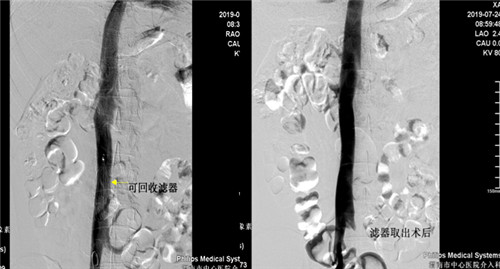

患者是一年轻男性,半年前因高血压性脑出血住院治疗,发现左下肢髂静脉股静脉腘静脉胫后胫前静脉血栓形成,由于脑出血有抗凝溶栓禁忌症,为预防肺栓塞的发生急诊行下腔静脉滤器(可回收)植入术,患者无脑出血后进行规范抗凝再无出血,超声复查下肢静脉血管未见新鲜血栓,D-二聚体正常,于7月24日早八点行经颈静脉下腔静脉滤器取出术,术后患者无腹痛发热出血等症状。

目前市中心医院对于下肢深静脉血栓形成患者常采用DENALI可回收下腔静脉滤器(最长回收时间窗632天)置入术预防肺栓塞的发生,该手术已在乐鱼在线登录入口广泛开展。但下腔静脉滤器取出术在渭南区域内尚未开展,市中心医院首次成功取出DENALI可回收下腔静脉滤器,标志着因担心滤器永久置入发生并发症而纠结放与不放的时代已结束,亦开创了渭南市血管介入新篇章,更好地为各科室的临床工作保驾护航,为更多的患者带来福音。